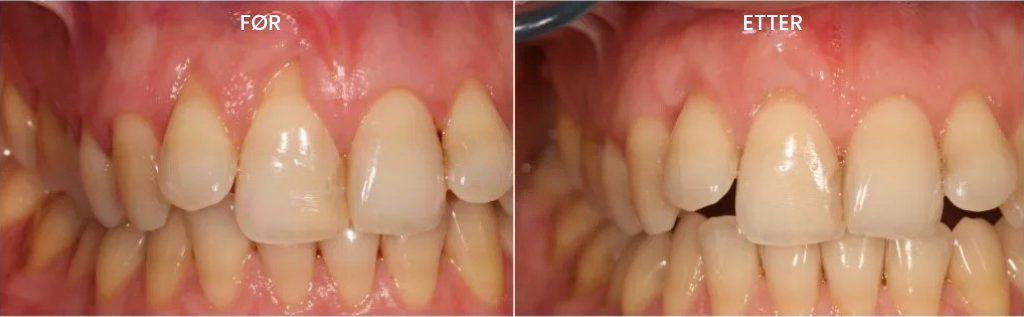

Teeth Repair Gel dekker det tilbaketrukne tannkjøttet og de blottlagte tannrøttene med et tynt, beskyttende lag hvis aktive partikler trenger direkte inn i de dype lagene av det tilbaketrukne tannkjøttet, nærer cellene og gir de "byggesteinene" som er nødvendige for vekst og reparasjon av sunt tannkjøttvev der tilbaketrekningen har skjedd.

De aktive komponentene i gelen erstatter de skadede cellene i tannkjøttvevet med lignende "byggesteiner", som utløser regenerering av nytt, sunt vev som dekker de eksponerte røttene som forårsaker følsomhet og smerte.

Dette gjør at du raskt og effektivt kan stoppe tannkjøtttilbaketrekning i alle stadier, gjenopprette helsen til tilbaketrukket tannkjøtt, styrke tennene til tannkjøttet, redusere følsomhet fra eksponerte røtter og forhindre videre tannkjøtttilbaketrekning som fører til tannløsning.

✅ Føl at det virker på tilbaketrukket tannkjøtt umiddelbart – Allerede etter 5–10 minutter vil du merke en betydelig lindring av følsomhet forårsaket av eksponerte tannrøtter, og etter noen dager vil du merke at det tilbaketrukne tannkjøttvevet begynner å gjenoppbygges og feste seg til tennene igjen. Ved regelmessig bruk vil du se at tannkjøttkanten gradvis kommer tilbake til en sunnere posisjon, og beskytter tennene dine mot farene ved tilbaketrukket tannkjøtt.